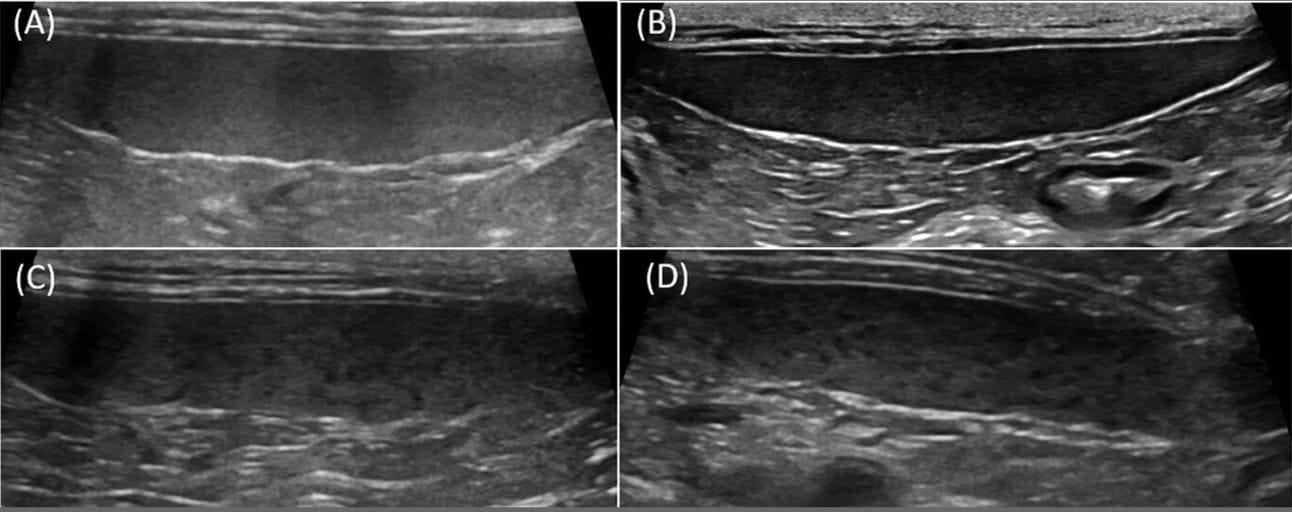

B-mode ultrasound images of reticulonodular pattern grades in apparently healthy kittens. (A) Grade 1—no nodules. (B) Grade 2—faint nodules affecting less than 10% of the spleen. (C) Grade 3—small nodules affecting 10%–25% of the spleen. (D) Grade 4—large nodules affecting more than 25% of the spleen. All images were obtained with a linear transducer at a frequency over 11 MHz.